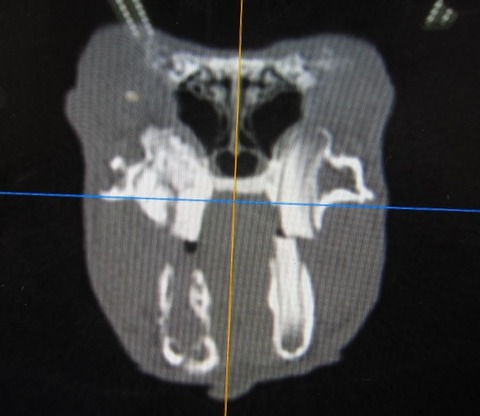

途中経過をCTで

まだまだたくさん残ってますが、👆これが👇こうなります。